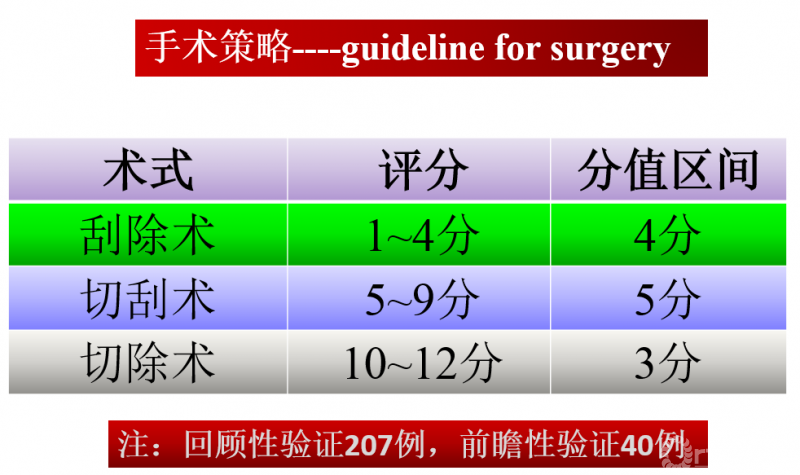

随即他联络国内12家各省级最大骨肿瘤治疗中心,于2009年成立中国骨巨细胞瘤协作组(GTOC),简称为“GTOC学组”。协作组通过成立课题研究小组、专家遴选进而初拟了指标体系的准备工作,又经过2轮的专家咨询、统计处理,进而完成Hu GCTS的构建。

在高水平循证医学证据缺失情况下,权威专家的共识观点是循证医学的关键所在。根据GTOC多中心流行病学数据统计,肿瘤关节假体置换手术占到股骨远端GCT病例总数的1/3(99例/302例)左右,学组专家纷纷表示此类患者的诊治需引起重视,在大家的共同努力下HU骨巨细胞瘤评分系统的建立,用于指导骨肿瘤科医生制定手术策略。

HU骨巨细胞瘤评分系统

手术策略的制定